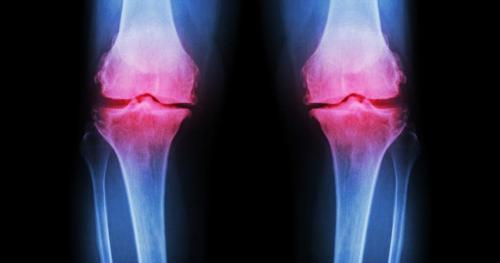

各位发现了吗?几乎所有发生骨质增生的部位,都与地心引力承重相关,颈椎-腰椎,髋关节,膝关节,踝关节及足跟,这些部位经过长时间的使用或过度使用(比如职业竞技选手),都会出现骨质增生现象,而骨刺本生的构造,就像我们的骨头是一模一样的,属于緻密型的结缔组织,其中也是蛋白质和钙离子等成分组成,因此我们应该将骨刺视为是人体的一部分,只是当我们出生的时候,这些结构并未出现,骨刺的出现,或许也是人类为了适应环境的挑战而衍生出来的防卫机制!

骨刺一旦出现即不可能消失,它最大的作用是为了让身体上的承重关节,进一步提升稳定度,比如膝关节,而骨刺增生所提示的另一个深层意义,代表身体机能的快速下降,因此我认为骨刺增生是人体最聪明的防卫机制,其实不是生病了,而是透过骨刺来提高我们能直立的本能.甚至保有行走的能力,所以我们并不需要去按摩或贴膏药来想着消除骨刺,因为这是不可能的,如果透过这些方法就能消除骨刺,那麽我们的骨头不也就同时被消灭了?想想这些广告真是挺有趣的.

只是,骨刺增生有好的一面,必然也可能有弊端,比如膝关节开始骨质增生,同时代表的是半月板开始丧失缓冲减震的能力,只好利用骨头来分担压力,同时因为骨刺占据了原本不应该存在的空间,使得关节腔变小变窄,而影响膝关节的关节动力学表现,比如肌力下降,关节活动度下降,无法蹲起,生活品质下降,甚至加大腰椎与髋关节的压力,引发一系列的不正确的代偿模式,各位发现了吗?膝关节疼痛的患者,75%以上都伴随着腰痛或腰椎间盘膨出现象,这都是人体的连锁反应,无可避免.